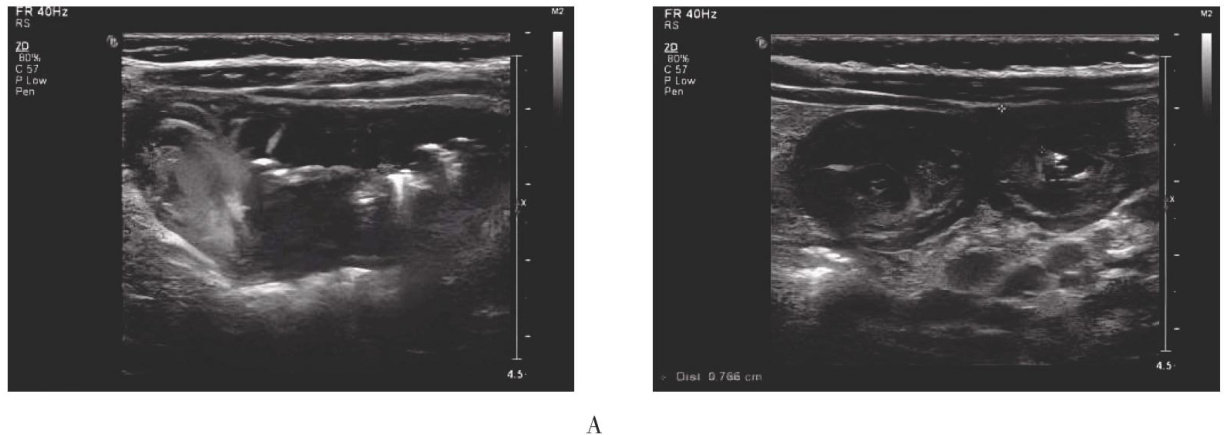

(DepartmentofUtrasound,epartmentofediatrics,AyuanCountyPeople'sHospital,Ayan4oo,Jiangi,ia) Abstract:Obetiealhrasocaesatisdseassfdoalcheuurainendoe diagnosticvalueofultrasoographyMethodsThelicaldataof62hidrenwithabdominalHenochSchonleinpurpuraoeretreatedn AnyuanCountyeople'sospitalfoarh toebruary2eeetrosptielyalydllpatintsundeetrsondaatio withspeialalpall ulrasoundasfdeioalouaealodgtofaltodts wredividedasltsd wall between the two groups was compared.Results Out of the 62 children,52 (83.87 % ) exhibited partial or extensive intestinal wall thickening with reducedoidallloso views.Corolerfneeadceaslodoalsitedetalallmadoalett twocaseshadsttll wasigifantlriostrotestialingoompadodouOocUrasodpf abdominalHenochnleinpurpuraaredisticti,withearvisualizationofestialwallhogenityndickengdingisee diagnosisurtheoretoisvasieaurendigprodulityultrasodisoreeptablrtsndit clinical applicability.

血管异常反应导致的过敏性紫癫主要侵袭7岁以下的幼童,表现为皮肤瘀斑、肠道出血和关节炎症等症状。(剩余4965字)